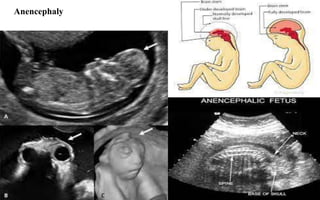

Anencephaly